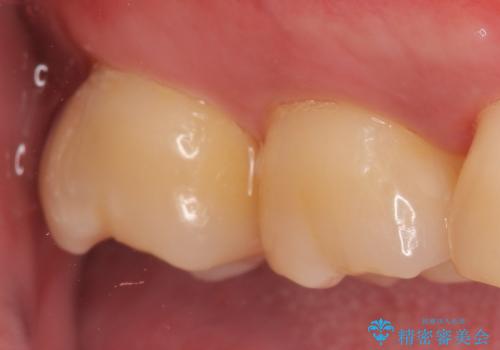

その後オールセラミッククラウンによる補綴を行いました。

今回用いたオールセラミッククラウンはジルコニアフレームという白い素材の上にセラミックを盛っているため、審美性が非常に高いのが特徴です。

また、ジルコニアは人工ダイヤモンドの材料にも使われているほど高い強度を持っており、そのためオールセラミッククラウンは審美性だけでなく、奥歯やブリッジの補綴も可能とするクラウンです。